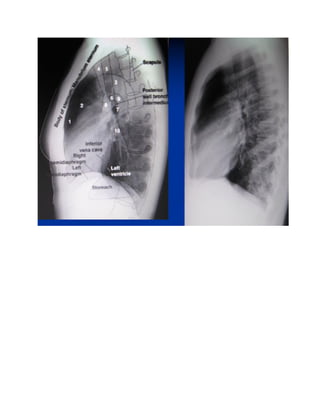

– Các cấu trúc bình thường trong lồng ngực .

1: Khí quản

2: PQ gốc phải

3: PQ gốc trái

4: ĐMP trái

5:ĐMP thùy trên

6:ĐMP thùy dưới

7:PQ gốc trái

8: Cung ĐMC

9: Thân TM tay đầu

10 :TM Azygos

– Các cấutrúc bình thường trong lồng ngực .

1: Khí quản 2:PQ gốc phải 3: PQ gốc trái 4: ĐMP trái 5:ĐMP thùy trên 6:ĐMP thùy dưới 7:PQ gốc trái 8: Cung ĐMC 9: Thân TM tay đầu 10 :TM Azygos